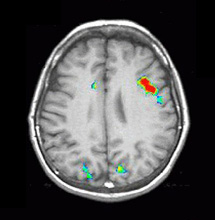

| Activación |

Se observa una activación en el área de Broca en ambos idiomas. La activación talámica derecha se observa solo en el segundo idioma. Se observa también una mayor activación de la circunvolución frontal inferior derecha en el segundo idioma que en la lengua materna. El área motora suplementaria es más pronunciada en la derecha en ambos idiomas. |